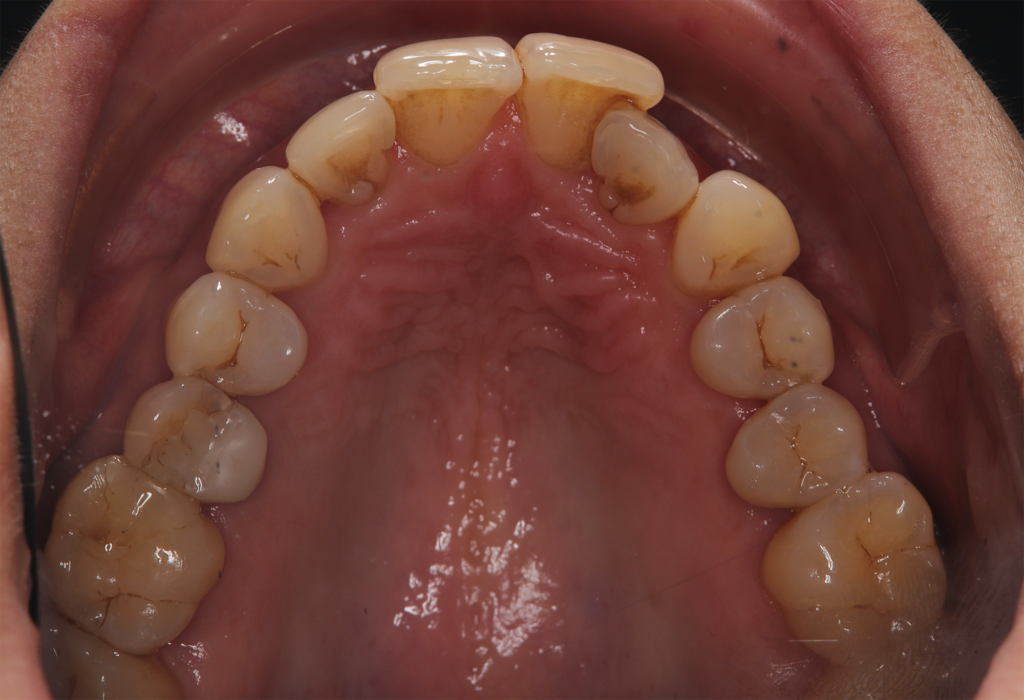

The patient, having completed a periodontal treatment phase, presented with significant aesthetic and functional concerns due to moderate crowding in both arches and a pronounced anterior crossbite. Clinical examination confirmed the need for comprehensive realignment, particularly in the anterior region. Although the patient had a history of periodontal issues, radiographic evaluation showed no signs of active disease. Based on these findings, the treatment plan was designed to carefully modulate orthodontic forces to protect the occlusion and surrounding tissues while addressing the misalignment.

To correct the misalignment and anterior crossbite without compromising tissue stability, a slower orthodontic treatment plan was devised using the Spark Advanced clear aligner system. The initial phase involved 36 aligners designed to gently expand and realign the dental arches, limiting the rate of tooth movement. Strategic interproximal reduction (IPR) was performed in the anterosuperior region (between teeth #21 and #11) to create the necessary space for proper alignment while avoiding excessive loading on the tissues.

To refine the results and enhance aesthetics, a second phase incorporating an additional 17 aligners was introduced. During this refinement stage, careful IPR in the lower arch helped harmonize the midline and achieve a balanced occlusion. Once satisfactory alignment was reached, provisional composite restorations were placed on the upper lateral incisors to aesthetically close any interproximal gaps.